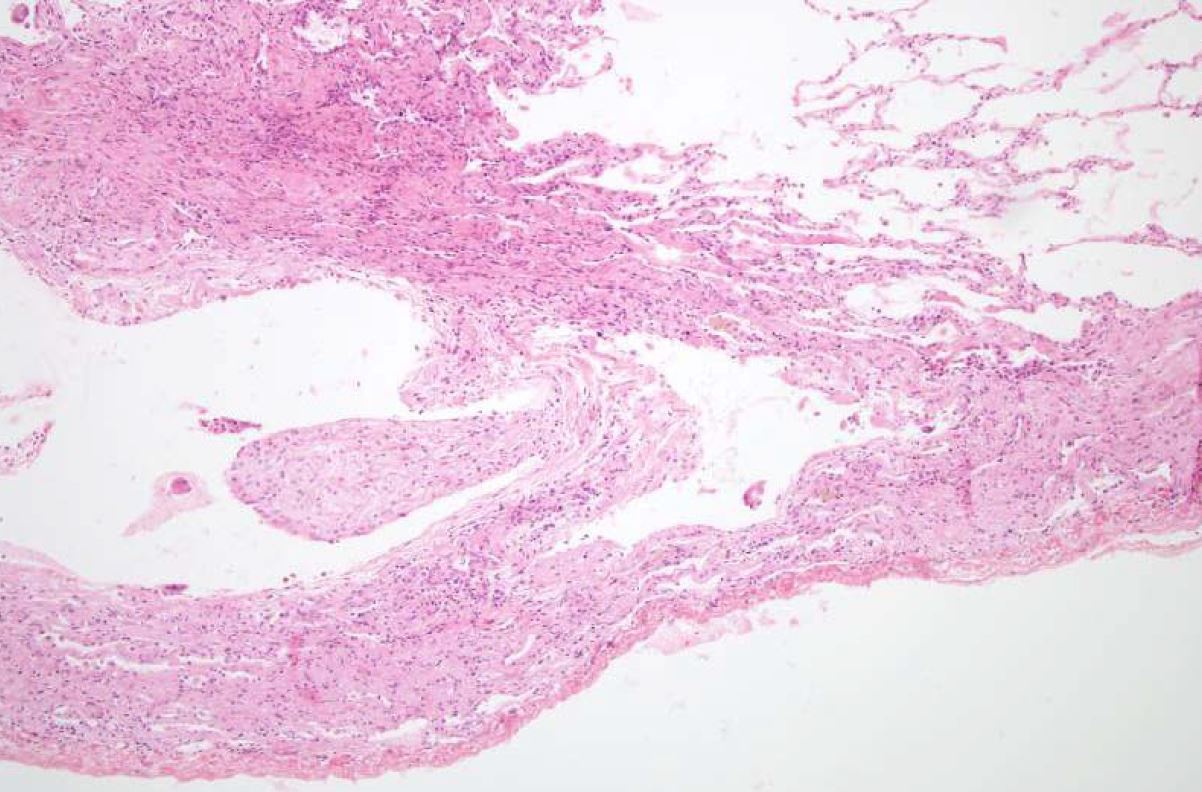

What is being shown here?

A

Pleural bleb in emphysema